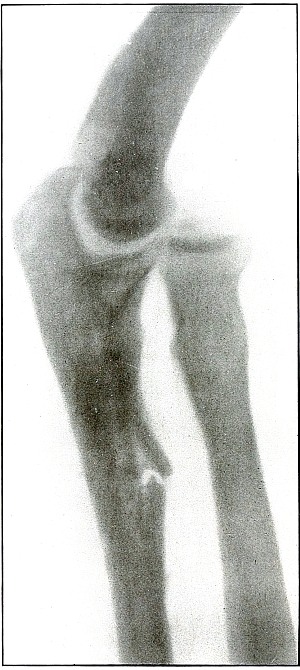

Gunshot fracture, elbow |

44 |

| 18. |

Gunshot fracture, elbow |

46 |

| 19. |

Gunshot fracture, elbow |

48 |

| 20. |

Gunshot fracture, elbow |

50 |